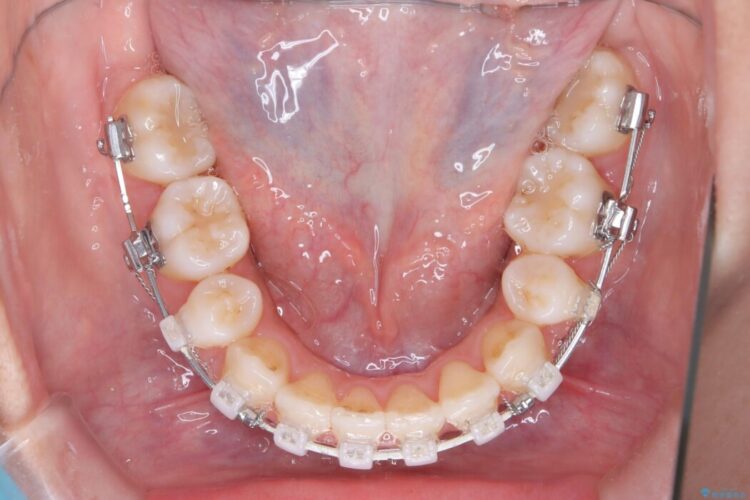

- 矯正装置:ワイヤー(審美装置)

装置は目立ちにくい審美ワイヤーを使用しています。

複雑に重なり合っていた前歯を、抜歯で作ったスペースを活用して丁寧に整列。単に並べるだけでなく、角度を1ミリ単位で調整しながら後ろへ下げることで、口元の突出感をスッキリ解消しました。